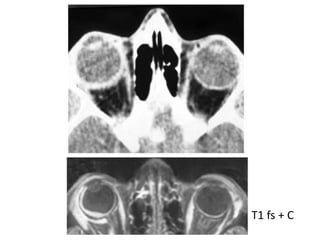

Scleritis

T1 fs + C